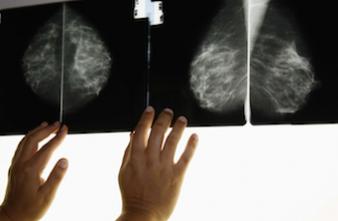

Cancer du sein

Mammographie : un résultat faux-positif ne détourne pas du dépistage

La découverte d’une anomalie à la mammographie démentie par les examens suivants angoisse les femmes mais ne les dissuade pas de continuer la surveillance.

- GUSTAFSSON/LEHTIKUVA OY/SIPA

Selon les chiffres de l’Institut national du cancer, 8 % des femmes qui participent au dépistage organisé du cancer du sein reçoivent un résultat faux-positif. La lecture immédiate de la mammographie révèle une anomalie, qui est démentie soit par la 2e lecture, soit par des examens complémentaires comme une nouvelle mammographie ou une biopsie. Une équipe de chercheurs américains a mené une étude auprès de plus de 1000 femmes pour comprendre ce que ressentent les femmes confrontées à ces résultats dits « faux-positifs » et si leur future participation aux programmes de dépistage du cancer du sein pouvait en être affectée.